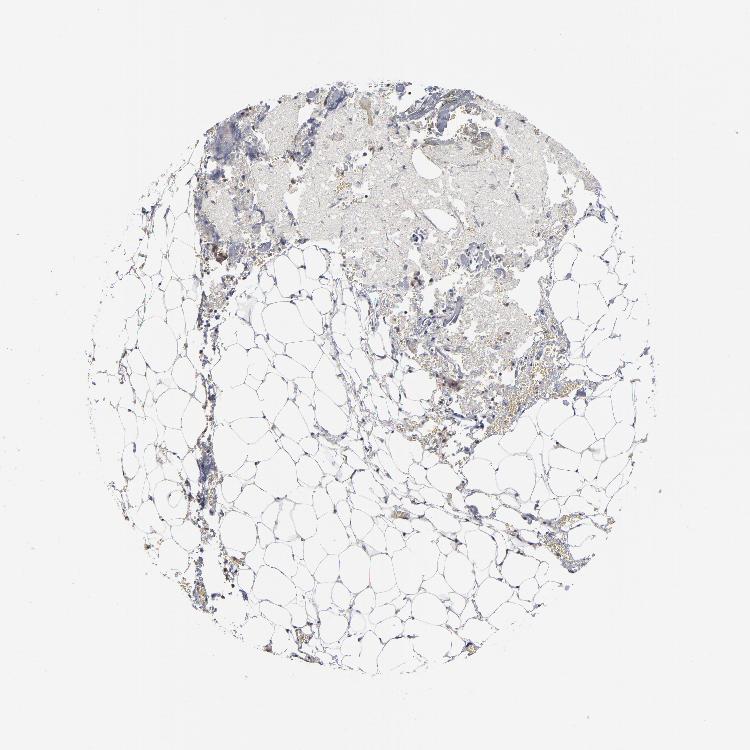

ADRENAL GLAND - Antibody stainingi

Antibody staining in the annotated cell types in the current human tissue is reported as not detected, low, medium, or high, based on conventional immunohistochemistry profiling in selected tissues. This score is based on the combination of the staining intensity and fraction of stained cells.

Each image is clickable and will lead to virtual microscopy that enables deeper exploration of all samples and also displays staining intensity scores, fraction scores and subcellular localization as well as patient and tissue information for each sample.

Antibody HPA003342Antibody HPA030411Antibody HPA030412Antibody CAB005103

Glandular cells MediumMediumLowMedium